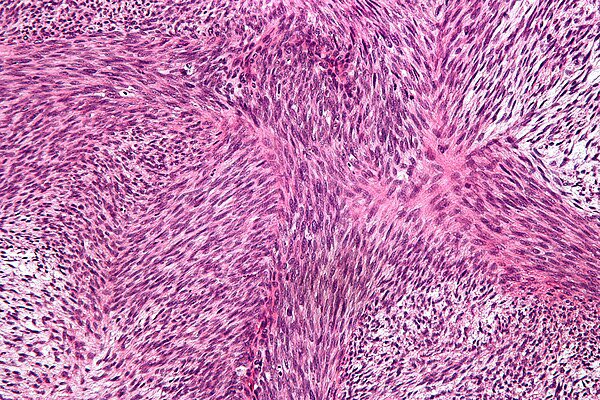

65 year old man posterior auricular neck deep dermal nodule. easy peezy?#dermpath #PathTwitter #dermatology Etan Marks, DO @ArjunRamaiya1 Lorand Kis Olaleke Folaranmi Tristan Rutland MBBS FRCPA IFCAP Trish Stratus Marcelasaeblima. Allison Osmond MD MSc FRCPC Ahmed Alomari, MD Gonzalo De Toro